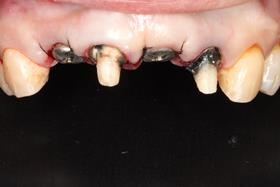

治療前,X光片及口內照片。

右上側門牙及左上正中門牙斷裂。

舊牙冠拆除後,舊牙冠拆除後,術後X光片。